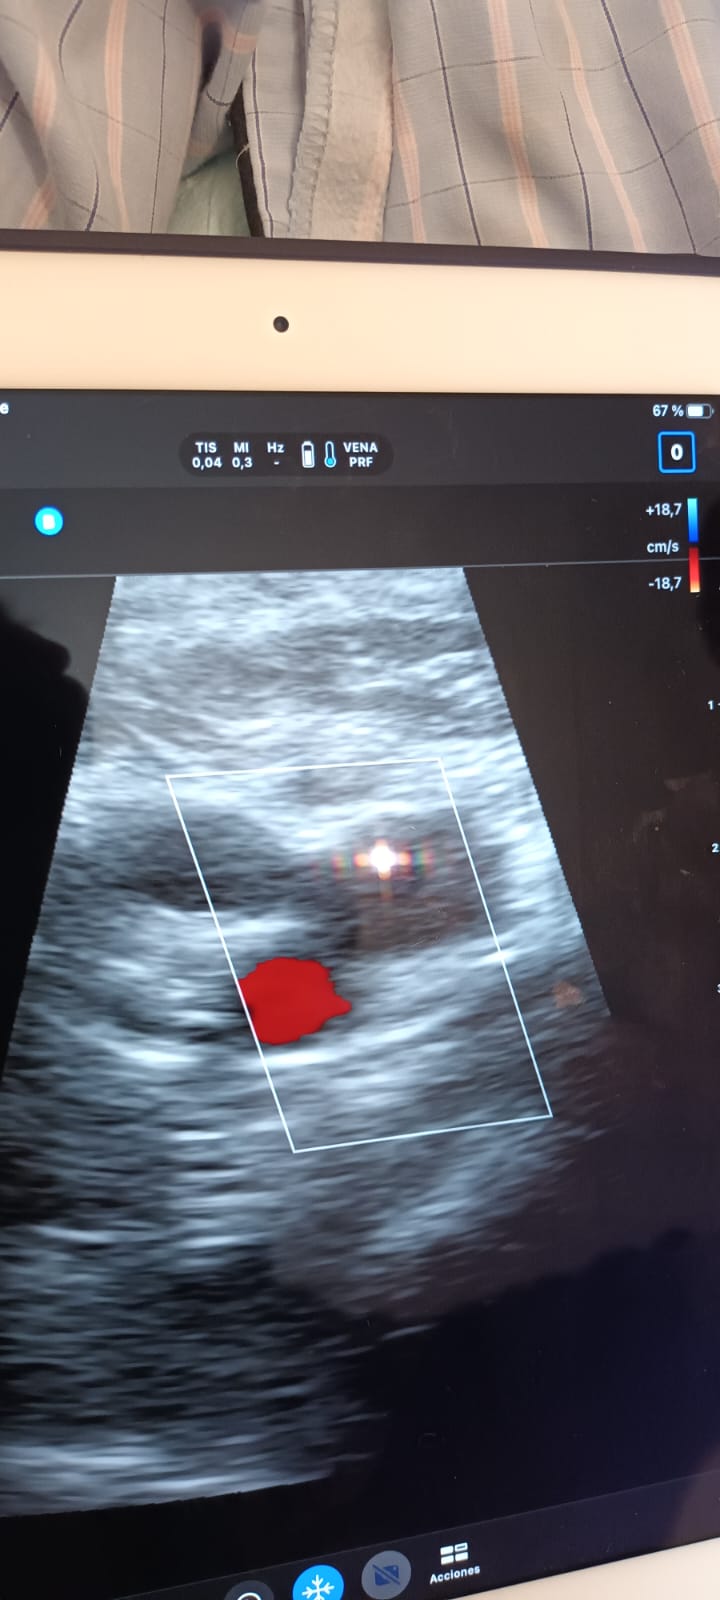

Al realizar ecografía Doppler miembro inferior derecho, objetivamos en región ilíaca, femoral, y poplítea, ocupación por material ecogénico, y que no resultan compresibles.